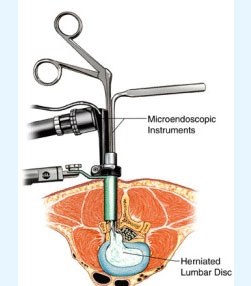

- Spine surgery - More than 3000 spinal surgeries including 40 spinal tumors microdiscectomy, MIS TLIF, artificial disc replacements, multilevel corpectomy, CV junction stabilization.